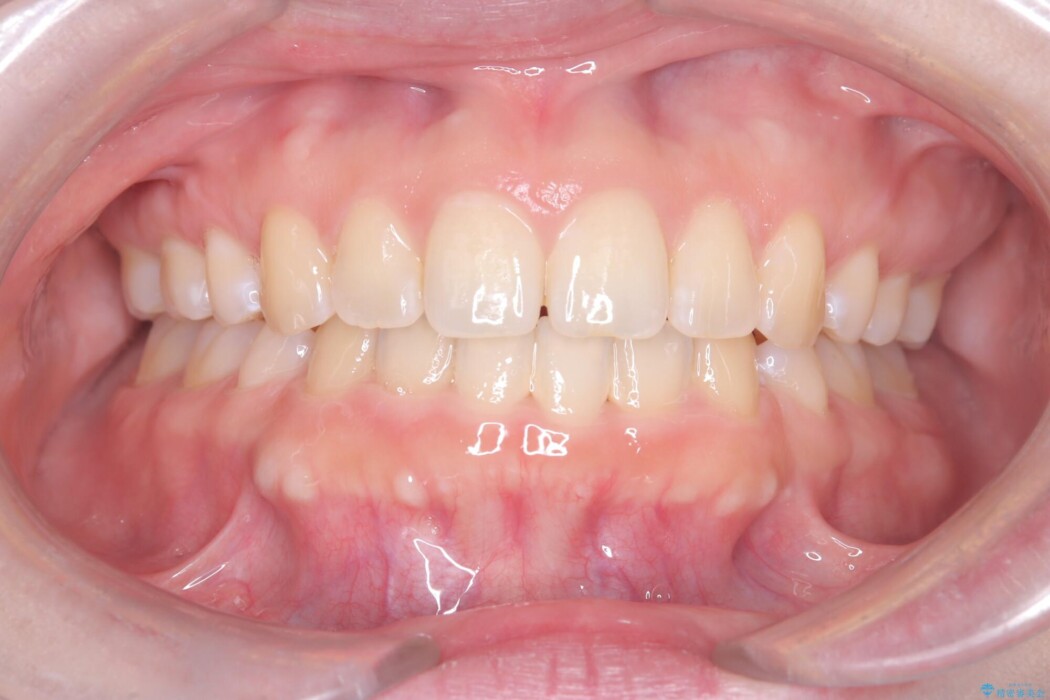

治療後について

抜歯で得たスペースを活用し、大きく傾いた前歯の角度を修正しながら、ゆっくりと後方へ移動させていきました。

抜歯スペースが閉じるにつれて、唇側の圧迫感が解消され、口元のボリュームが自然に抑えられていきました。

治療後は、口元の突出感が解消され、鼻先から顎先を結ぶ「Eライン」が劇的に変化し「自信を持って笑えるようになった」と大変喜んでいただけました。